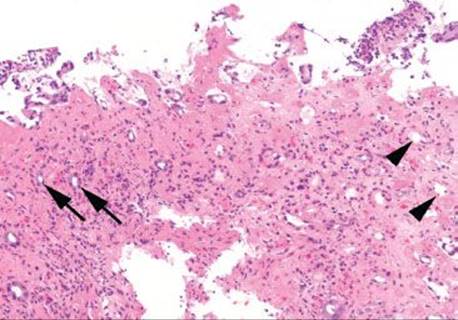

Figure 4.57 Ischemic colitis pattern, microcrypts. Microcrypts with residual withered epithelium can be seen at the left (arrows), while crypts that have completely lost their epithelium are seen on the right (arrowheads). Again, note the quality of the lamina propria, which appears densely pink, rather than the typical colorless (or white) appearance.

Decreased blood flow and lack of oxygen to the GI tract result in necrosis or tissue damage, causing ischemia. There are several weak points in the colonic blood supply, known as watershed areas, which result from incomplete anastomosis of the marginal arteries and lack of sufficient collateral circulation. These watershed areas are more vulnerable to ischemic injury than other parts of the colon and include the splenic flexure (or Griffith’s point), the rectosigmoid region at Sudeck’s point, and the ileocecal region. Among the older population, ischemic disease is typically attributable to atherosclerotic mesenteric vascular disease, but the causes of colonic ischemia are many (Table 4.2). The histologic findings are dependent on the timing of the ischemic event (Figs. 4.52–4.63). Early and minimal injury, for example, occurs first as degeneration and sloughing of superficial epithelial cells, edema, and vascular congestion. Later, the epithelial cells become markedly attenuated and the crypts appear compressed and atrophic (“microcrypts”) as the lamina propria swells and hemorrhages. Within 5 hours of total acute vascular occlusion, almost the entire intestinal wall appears necrotic. These changes are devoid of acute inflammation until reperfusion occurs. Paradoxically, reperfusion further injures the tissues by introducing oxygen free radical formation,16 the severity of which is dependent on the duration of the preceding hypoxia.

Mucosal ischemia causes a highly characteristic pattern of injury, including features of surface injury, loss of mucin, lamina propria hemorrhage and hyalinization, withered crypts, atrophic microcrypts, and lamina propria collapse (Fig. 4.50). The architectural pattern of withered crypts and microcrypts is distinctive at low magnification, and one might even refer to this pattern of injury as the “microcrypt pattern” (Fig. 4.51). Although ischemic injury is top among the differential diagnoses, other considerations include vascular injury (such as that seen in radiation colitis, amyloidosis, or vasculitis), infection (particularly Escherichia coli 0157:H7 and Clostridium difficile), and medications (NSAIDs, Kayexalate, and sevelamer).